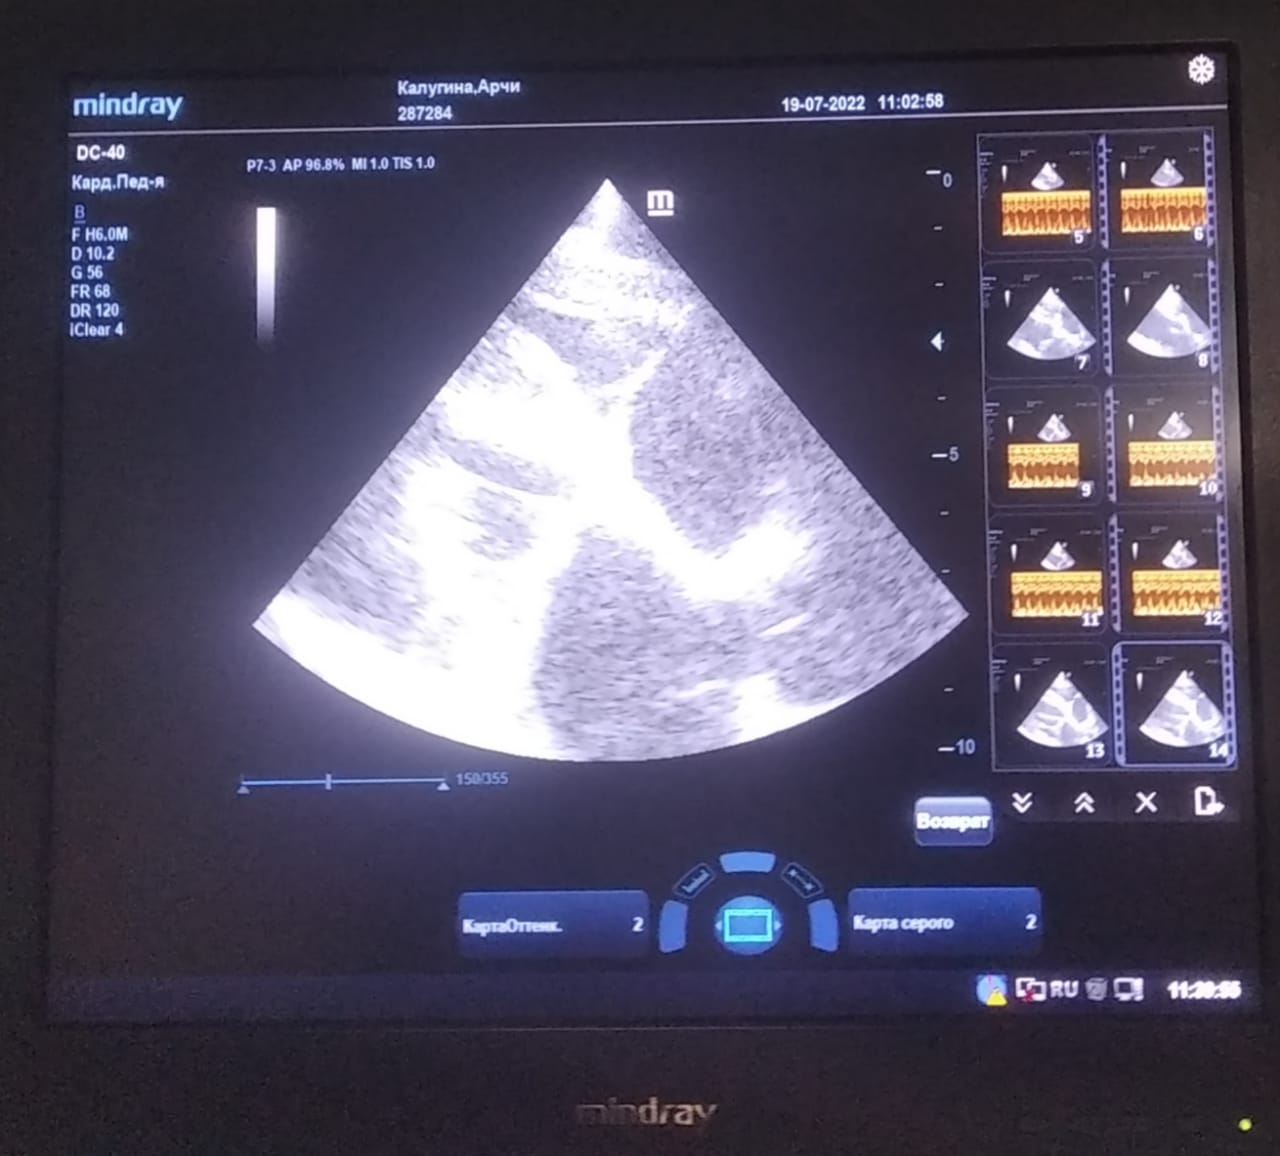

Анализы Арчи. Сердца и легких

Вложения

IMG-20220719-WA0100.jpg

IMG-20220719-WA0102.jpg

IMG-20220719-WA0104.jpg

IMG-20220719-WA0103.jpg

IMG-20220719-WA0105.jpg